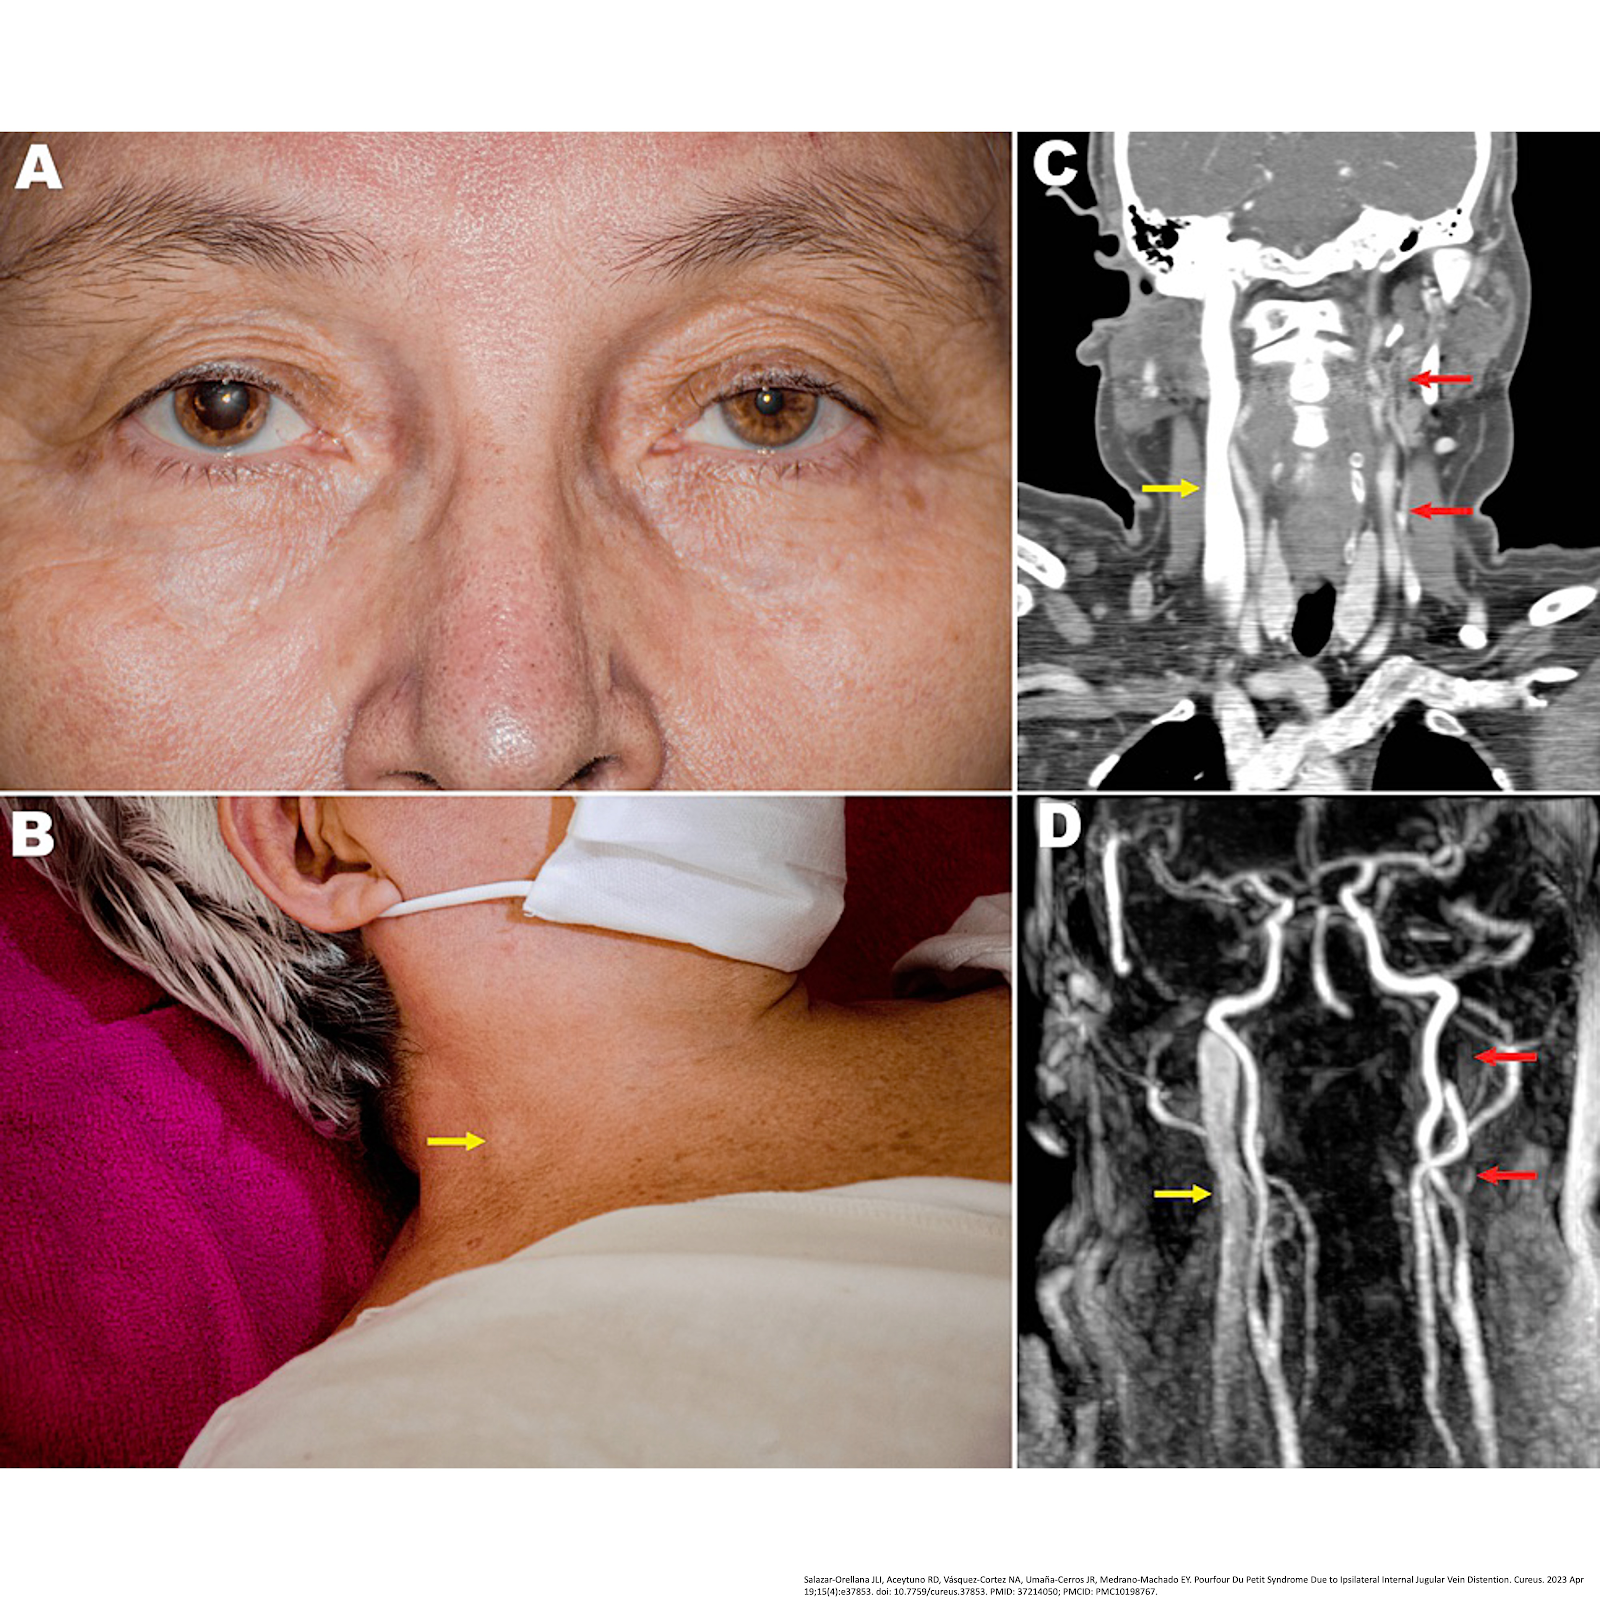

5.7. PPS due to ipsilateral IJV distention

A) Day 5 after thyroid surgery, with right mydriasis and ipsilateral upper eyelid retraction.

B) Follow-up 2 months after thyroid surgery, with complete resolution